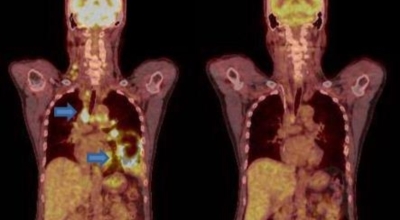

폐암 검사는 X-ray를 통해서 검사하는데 , 크기가 작거나 구석에 위치한 경우 확인이 어려운 경우도 있습니다. 그리고 조직 검사를 통해서 정확한 진단을 하게 돼요. 폐암이 발견되면 종양의 크기나 전이 여부 , 위치에 따라서 수술 여부를 결정하게 돼요.

수술 치료

악성 종양이 있는 폐의 일부를 절제하는 방법입니다. 초기에는 내시경 기구를 활용하여 수술이 가능하기도 해요.

항암 치료

항암제를 이용한 치료 방법입니다. 폐암 4기 같은 경우에는 항암 화학요법이 유일한 치료방법이기도 해요. 폐암에 대하여 알아봤는데요.